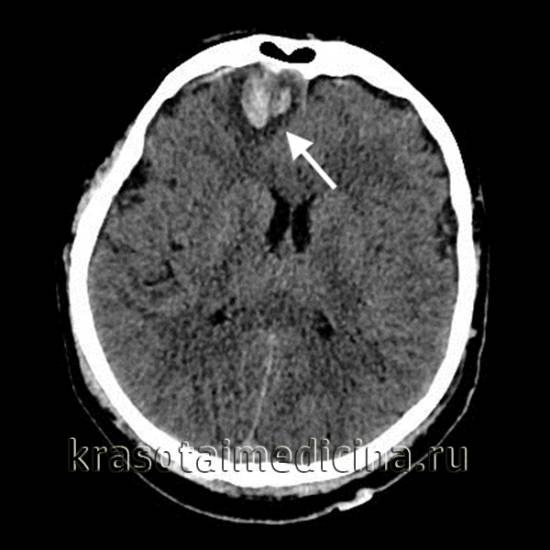

image

Аксиальная КТ головного мозга без контрастного усиления. Определяется контузионный очаг в правой лобной доле, представленный геморрагическим компонентом, зоной детрита и отека

Ушиб средней тяжести характеризуется наличием на томограммах очагов ушиба в виде зон пониженной плотности. При геморрагическом пропитывании очаг ушиба может иметь повышенную плотность. При тяжелом ушибе томография визуализирует очаги как повышенной, так и пониженной плотности. В первом случае речь идет о сгустках крови, во втором — об участках размозжения и отека. При крайне тяжелых поражениях зона деструкции церебральной ткани уходит вглубь к подкорковым структурам.